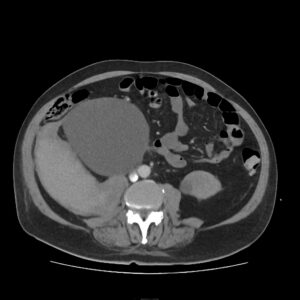

Radiology Expertise

Our team includes highly skilled professionals, ensuring accurate and timely diagnoses. If you need a radiologist for ultrasound in Delhi, Dr Wadhwa Ultrasound CliniQ & Lab is the place to visit. From colour Doppler ultrasound in Delhi to general imaging, we ensure every scan meets international standards. The colour Doppler service is particularly beneficial for assessing blood flow in arteries and veins, vital for detecting conditions like deep vein thrombosis or blockages.